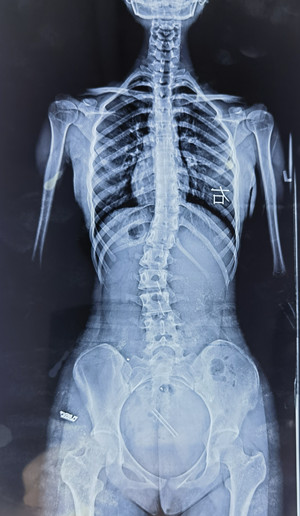

脊柱側(cè)彎的X線檢查

通過全脊柱正、側(cè)位X線檢查,能明確側(cè)彎的部位、角度、性質(zhì)、椎體旋轉(zhuǎn)程度等。要避免僅拍攝脊柱單部位X線片,因為其難以充分顯示脊柱全貌,對診斷脊柱側(cè)彎來說是局限的。

在X線檢查中,我們可以測定患者的cobb角,該角度測量是通過測量脊柱上下彎曲最頂端的兩個椎體上、下緣所成的角度,來確定側(cè)彎的嚴(yán)重程度。